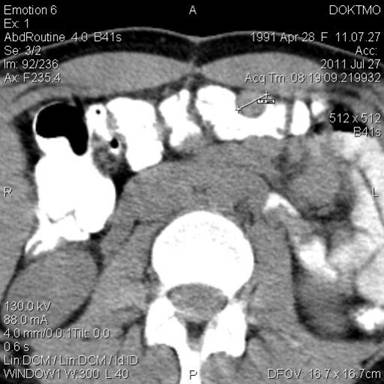

In July 2011, spiral CT of abdomen and retroperitoneum with preliminary per os contrast (Figure 1) showed soft-tissue formation with clear, irregular circuits 3.6×2.0 cm in size in the projection of bed of the rejected spleen; rounded soft-tissue formations, with smooth, clear circuits, up to 0.9-1.3 cm in size were detected parasagittally in abdomen, under the anterior abdominal wall at the level of L2-L4. Conclusion: formations in abdomen of above-described localization may appear due to the enlarged lymph nodes? Remaining slices of the rejected spleen? CT with intravenous bolus enhancement is recommended in order to exclude neoplastic genesis.

Figure 1. Spiral CT of abdomen and retroperitoneum with preliminary per os contrast. Rounded soft-tissue formations are detected parasagittally in abdomen, under the anterior abdominal wall at the level of L2-L4 (splenosis?). |